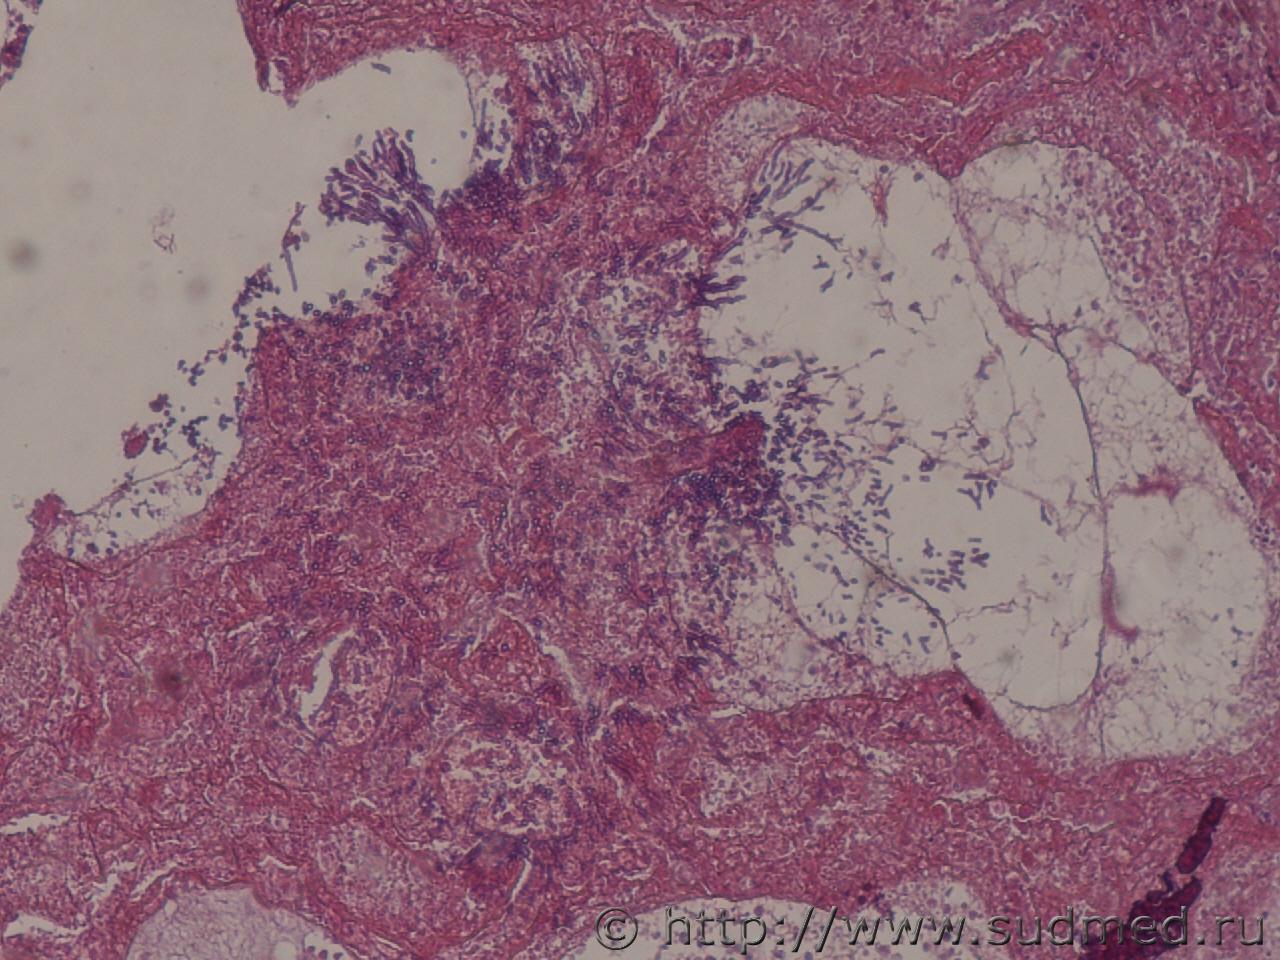

Негнойный аспергиллёз легких

Судебная медицина - Прикрепленное изображение Судебная медицина - Прикрепленное изображениеСудебная медицина - Прикрепленное изображение

БИН-синдром

Судебная медицина - Прикрепленное изображение